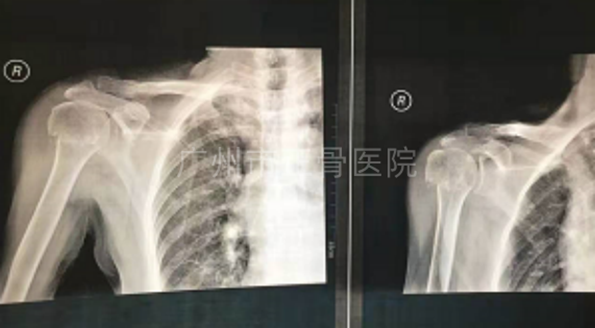

辅助检查:X线片示:右肱骨外科颈骨折,骨折远端向内移位。

诊断:右肱骨外科颈骨折。

▲伤后X线,骨折移位